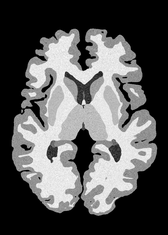

4.2 Registration to a 100 micron ex-vivo brain MRI volume

To showcase the efficacy of our method on real large scale images, we register a 250 in-vivo MRI image (Lüsebrink et al., 2017) to a 100 ex-vivo FLASH human brain volume (Edlow et al., 2019). This represents an inverse problem with more than 11.2B optimizable parameters (compared to 20M for clinical datasets), or 44.8GB of GPU memory. The entire problem does not fit on most GPUs, necessitating distributed multimodal registration. We optimize a composite transform - affine followed by a diffeomorphic mapping; details can be found in Section E.1. Multimodal deformable registration took 58 seconds on 8 NVIDIA A6000 GPUs, which is unprecedented at this resolution. Fig. 6 shows qualitative results, highlighting the ability to register highly detailed structures such as cerebellar white matter; these structures are not visible at macroscopic scales. The resultant advantages of performing registration at this scale can allow researchers to characterize the neuroanatomy at microscopic resolutions and allow morphometric analysis of cortical layers and subcortical nuclei among other structures.